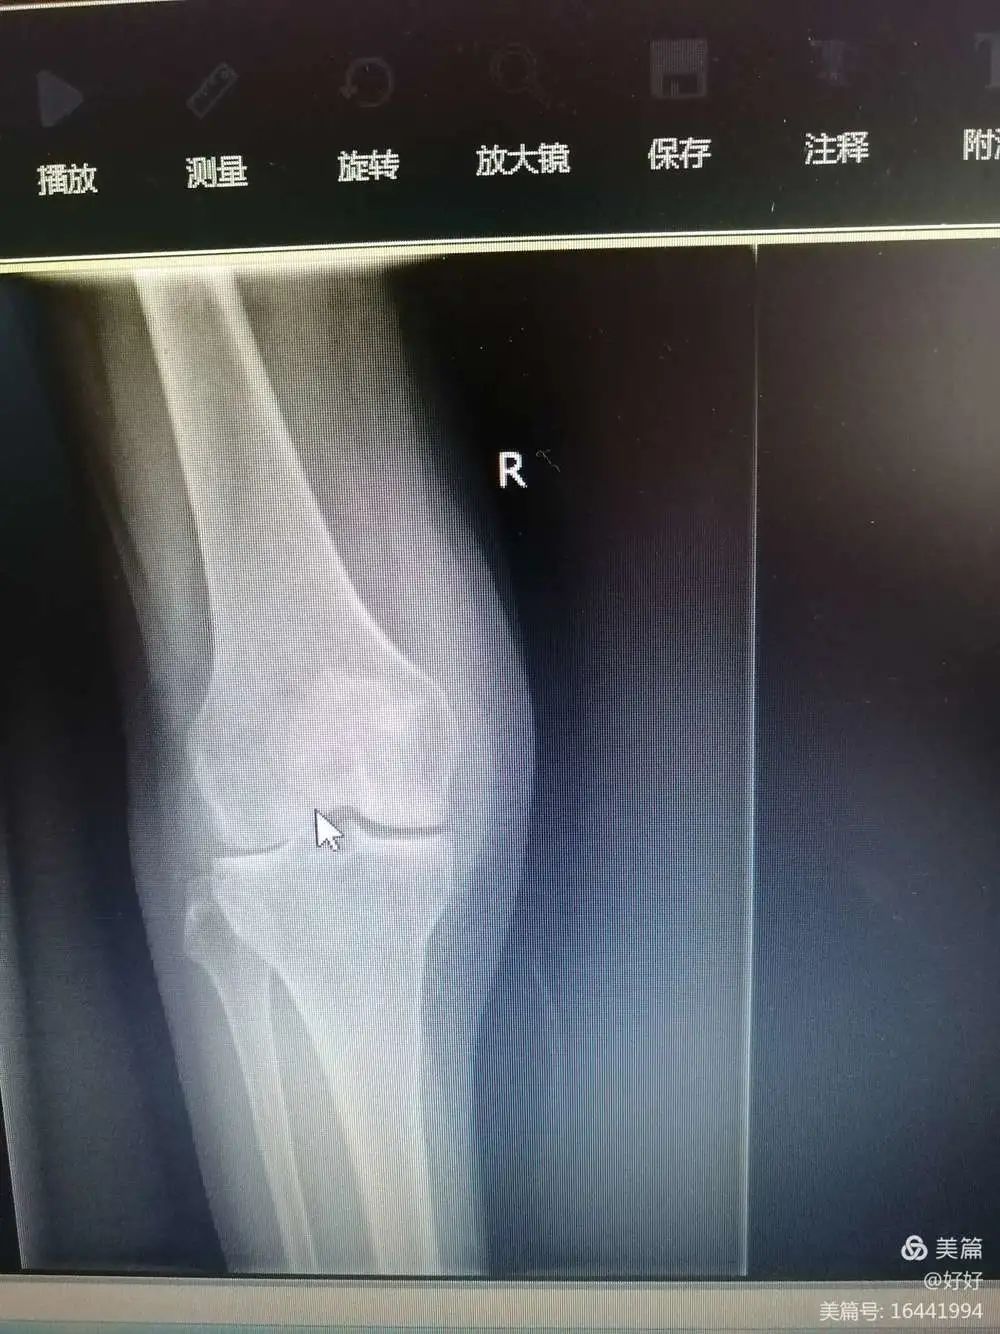

术前X线

李XX,男,55岁,外伤导致右膝关节疼痛30余年,患者30年前右小腿骨折,未行正确治疗,右膝关节活动完全受限,无法正常行走及日常生活,我科骨科团队予以行右膝人工关节置换,术后患者可以正常走路,且从事正常劳作。